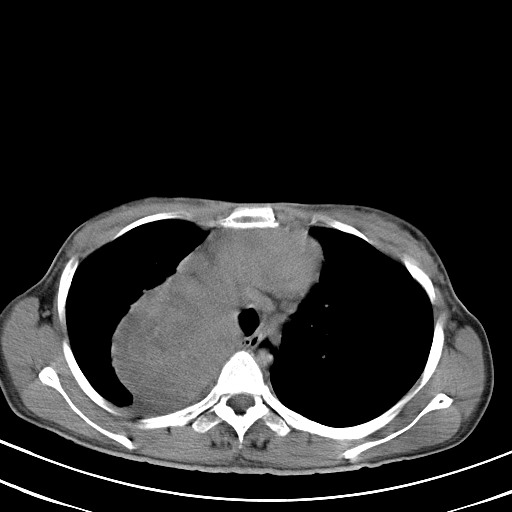

以下是引用汪涛同志在2007-8-2 0:40:00的发言:[br]病变虽然广泛,同时侵及双侧纵隔,但是无论左侧和右侧上下观察都是与右侧颈部甲状腺相延续的,而且强化幅度基本一致,又同时具有恶性病变病变的某些特征:肿块过大且密度不均,部分层面与正常纵隔结构分界不清,结合病史已有两年,考虑:胸内甲状腺肿恶变可能。[br]